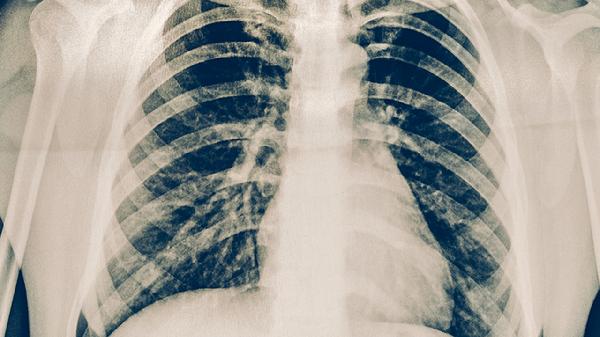

西黄胶囊是一种中成药,主要成分包括牛黄、麝香等,具有清热解毒、消肿散结的功效。在肺癌治疗中,西黄胶囊可能有助于缓解部分症状,但具体疗效受多种因素影响。肺癌的治疗需要综合考虑肿瘤类型、分期、患者身体状况等因素,西黄胶囊通常不作为主要治疗手段,而是作为辅助治疗药物使用。

对于早期肺癌患者,手术切除是首选治疗方法,此时西黄胶囊可能帮助术后恢复。中期肺癌患者在接受放化疗时,西黄胶囊或可减轻治疗带来的不良反应。晚期肺癌患者以姑息治疗为主,西黄胶囊可能改善生活质量。但需注意,西黄胶囊对肿瘤细胞的直接抑制作用有限,不能替代规范化的抗肿瘤治疗。个别患者可能出现药物过敏等不良反应,需在医生指导下使用。